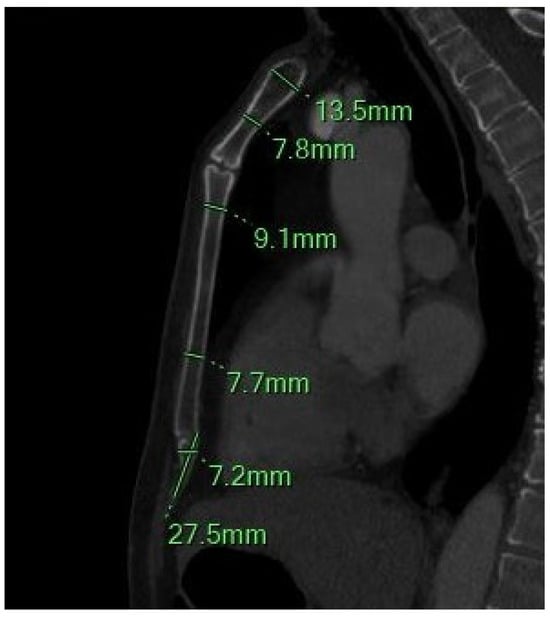

Figure 2.

The sagittal MIP MPR image shows the minimum and maximum thickness of the manubrium, the thickness of the sternal body between the 2–3 and 4–5 sternebrae, and the length and width of the xiphoid process.